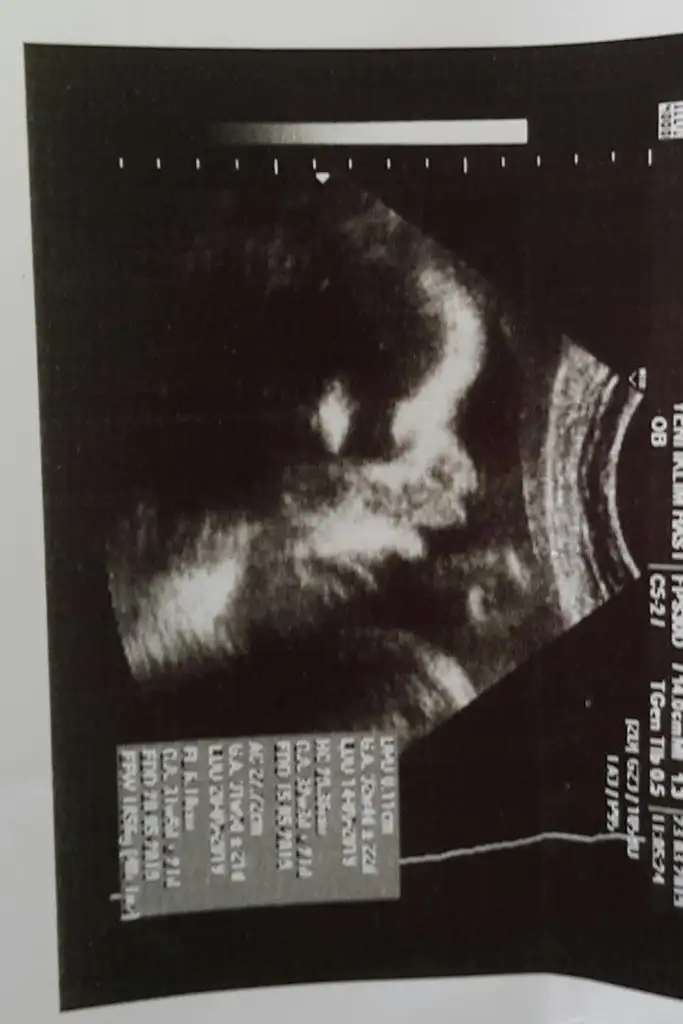

1.5 ay sonra kontrole gittim

çok çok şükürler olsun şükür namazı lazım bana

Bebeğim çok güzel gelişmiş

1.850 kg olmuş Allahım sana şükürler olsun.

arayı kapatmış maşallah subhanAllah.

doğum pozisyonunda. Doktorum çok güzel ilgilendi , tekrar 1 ay sonra gideceğim 37 haftada inşallah.

ve kızım dilber dudaklarını uzatıp hareket ettirip durdu. büyükler gibi minik dudaklı olmayacak galiba. şeker kızım benim.

kızlar kızımın dudak resmini yollayayım Sizede

bayan dilber dudak